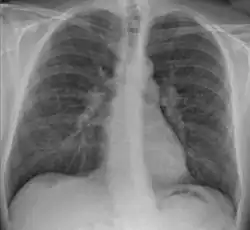

Chest X-ray showing the typical nodularity of sarcoidosis, predominantly in the hila of the lungs.